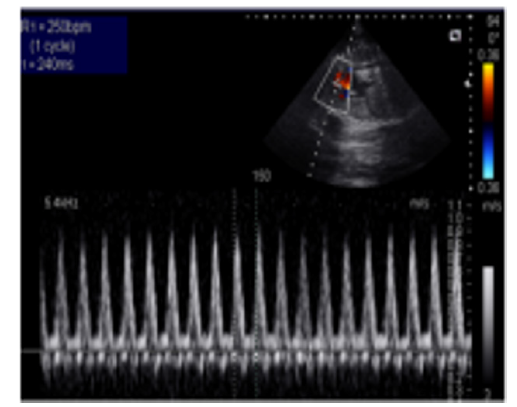

A 35-year-old pregnant woman being in the 29th Gestational Week (GW) was admitted to the Department of Obstetrics and Gynecology of University of Szeged, due to fetal tachycardia with a Fetal Heart Rate (FHR) of 250/min. The mother suffered from hypertension before the pregnancy and underwent calcium channel blocker therapy (Verapamil), which was replaced with methyldopa (Dopegyt) during the pregnancy. Nuchal translucency and biomarkers measured in the first trimester were normal. There was no positive family history for Congenital Heart Defect (CHD). A fetal echocardiography was performed, according to the AIUM guidelines [1]. The FHR was between 240-260/min, the Atrio-Ventricular (AV) conduction was 1:1, a Supraventricular Tachycardia (SVT) was diagnosed (Figure 1). Fetal echocardiography revealed an abnormal four-chamber view, a very large right atrium and a very small right ventricle, the tricuspid valve was abnormal, attached deeply in the right ventricle and the apical displacement of the valve led to the atrialization of the right ventricle and a holosystolic tricuspid regurgitation could be detected by Doppler. The pulmonary artery was very narrow, the diameter of the aorta was twice as big as the diameter of the pulmonary artery, therefore a duct-dependent CHD with decreased pulmonary circulation was suspected. The abnormal anatomy of the fetal heart was characteristic for Ebstein anomaly (Figure 2), which is a complex cyanotic CHD. Pericardial or pleural effusion was not observed, but some ascites was already seen in the abdominal cavity (Figure 3), indicative of incipient fetal heart failure.

Figure 1:Supraventricular tachycardia in a 29 GW old fetus. FHR. 250/min.